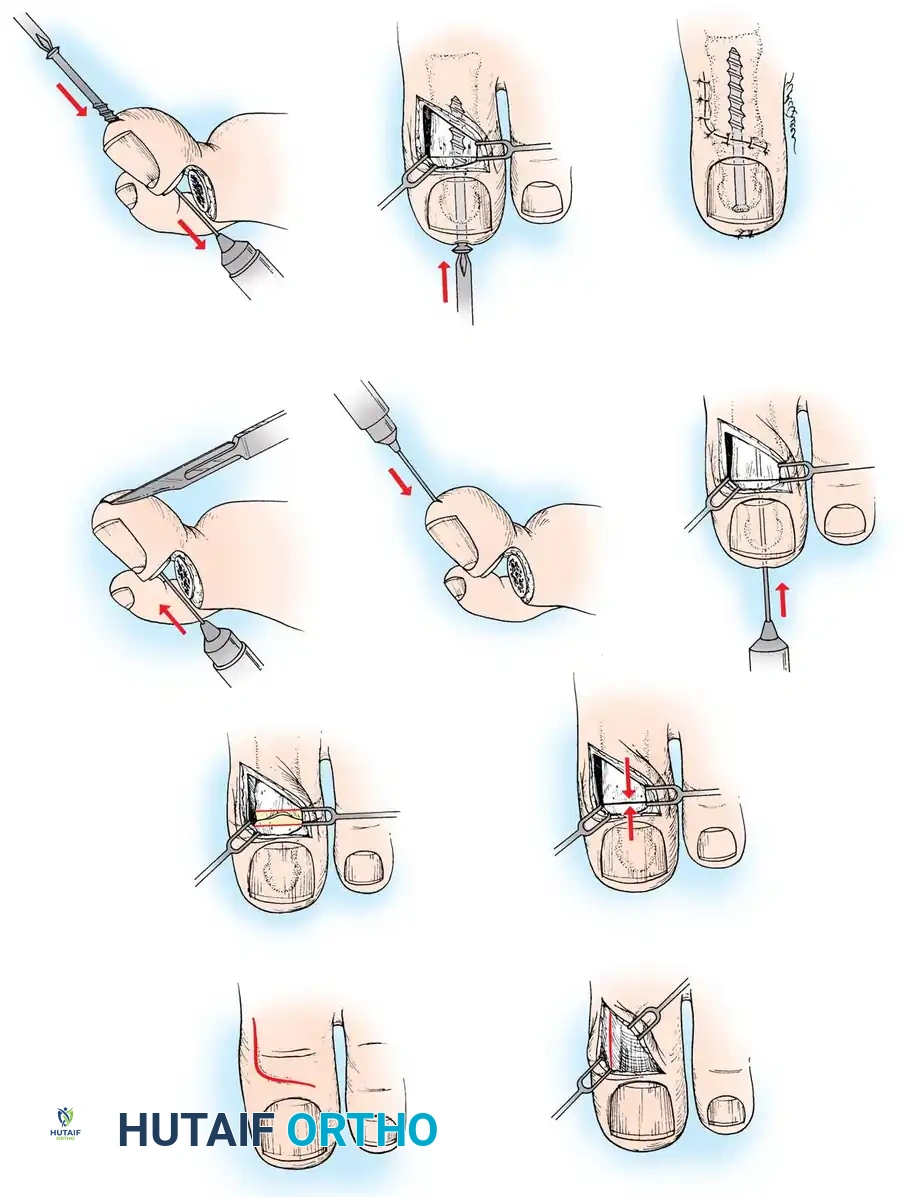

FIBULAR SESAMOIDECTOMY: PLANTAR APPROACH

• If a plantar approach (Fig. 78-21A) is chosen for fi bular sesamoidectomy, have an assistant hold the ankle dorsifl exed, and use a headlight for seeing into the full depth of the wound. Avoid the fl exor hallucis longus tendon and the neurovascular bundle to the fi rst web space.

• Flex and extend the hallux, and inspect the radiograph to locate the sesamoid. Beginning 1 to 1.5 cm distal to the metatarsophalangeal joint, make a longitudinal incision in the plantar surface of the foot, extending the incision proximally 3.5 to 4 cm between the fi rst and second metatarsals.

• If the fi bular sesamoid requires excision, it usually is subluxed.

• When the skin and fascial septa within the forefoot pad have been separated, insert a small self-retaining retractor.

• Using small, blunt-tip dissecting scissors, identify the neurovascular bundle to the fi rst web space, and retract it laterally or medially, depending on the position of the sesamoid (Fig. 78-21B).

• Palpate the sesamoids, and fl ex and extend the hallux to locate the fl exor hallucis longus tendon.

• Open the pulley over the fl exor hallucis longus tendon, and retract the tendon medially. This maneuver is made easier by having an assistant hold the foot in dorsifl exion at the arch with one hand and fl ex the metatarsophalangeal joint to relax the fl exor hallucis longus tendon with the opposite hand.

• At this point, the intersesamoid ligament should come into view; divide it completely (Fig. 78-21C). This may require moving the scalpel 1 or 2 mm laterally or medially to fi nd the groove between the sesamoids.

• Incise the cleavage plane between the two sesamoids, while retracting the fl exor hallucis longus muscle medially and the neurovascular bundle laterally.

• Grasp the fi bular sesamoid with a strong pick-up or small Kocher clamp, and remove the lateral head insertion of the fl exor hallucis brevis muscle on the proximal end of the sesamoid using direct vision (loupe magnifi cation makes this easier, but is not necessary).

• When the medial and proximal restraints of the sesamoid have been released, sever the attachment of the adductor hallucis muscle to its lateral distal edge close to the bone with a scalpel or scissors.

• Sever the last attachment of the sesamoid distally where the plantar plate continues its distal insertion into the proximal phalanx (Fig. 78-21D).

• When the sesamoid has been removed, inspect the wound carefully for any bleeding. Pressing on the edges of the wound helps identify any potential bleeding vessels, which should be cauterized.

• Excising the sesamoid does not release the adductor insertion on the base of the proximal phalanx. This can be released through the plantar incision. Continuing to retract the neurovascular bundle laterally and the fl exor hallucis longus muscle medially, and adducting the hallux, while the opposite index fi nger palpates the adductor, helps identify the structure (Fig. 78-21E).

• Using right-angle retractors, expose the adductor, excise a small section of the tendon, and move the hallux medially.

• At the conclusion of this procedure, the surgeon should be unable to palpate any restraining structures on the fi bular side of the metatarsophalangeal joint. The transverse natatory fi bers in the dorsal aspect of the web space should be released manually. All restraints pulling the hallux laterally (except the extrinsic tendons) must be removed.

• Inspect the neurovascular bundle and the fl exor hallucis longus tendon.*

A

B

Fig. 78-21 Fibular sesamoidectomy (plantar approach). A, Incision. B, Common digital nerve to fi rst web space.

C D

E

F

Fig. 78-21, cont’d C, Flexor hallucis longus tendon is retracted medially, and neurovascular bun– dle is retracted laterally; intersesamoid ligament is divided. D, Fibular sesamoid ligament is removed, and lateral border of tibial sesamoid is exposed. E, Tendon of oblique head of adductor hallucis. F, Healed plantar incision.